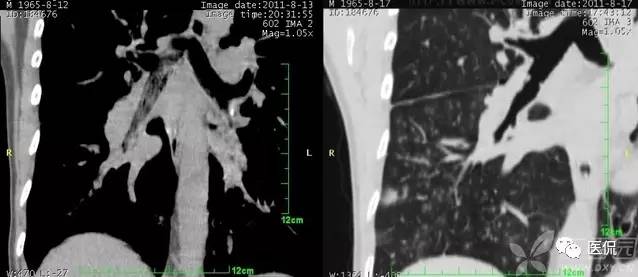

碎石路征

碎石路征或称铺路石征,是胸部CT上的一种影像学征象,主要表现为在弥漫性或散在分布的毛玻璃样浸润影中,有小叶间隔增厚、小叶内线状影重叠存在。碎石路征最初在肺泡蛋白沉积症(PAP)的病例中发现,并认为是PAP特征性的胸部CT表现;但实际上,感染性疾病、肿瘤、特发性肺弥漫性疾病(DPLD)、吸人性病变等都也可以出现。

1)PAP是一种罕见病。各个年龄均可发病,以20~50岁的成年人多见。干咳、呼吸困难是其最常见的临床症状,而胸膜性胸痛、乏力、低热等则较少见。其胸部X光片表现是双侧对称性的肺泡实变或毛玻璃影,主要分布于肺门及肺门周围而类似肺水肿。CT的典型表现包括:①毛玻璃影及实变影与小叶间隔增厚交织形成碎石路征样改变;②在肺泡实变与正常的肺实质之间出现很明显的分界线,形成“地图样”分布。PAP碎石路征的组织学基础是:毛玻璃影及实变影与肺泡内充满PAS染色阳性、富含脂质的蛋白样物质有关;小叶间隔增厚影与肺泡壁因纤维组织增生或II型肺泡上皮细胞增生及淋巴细胞浸润有关。依据碎石路征和“地图样”分布,结合患者临床与影像学表现不平行的特点,是诊断PAP的诊断的不要依据。

典型的肺泡蛋白沉积症: